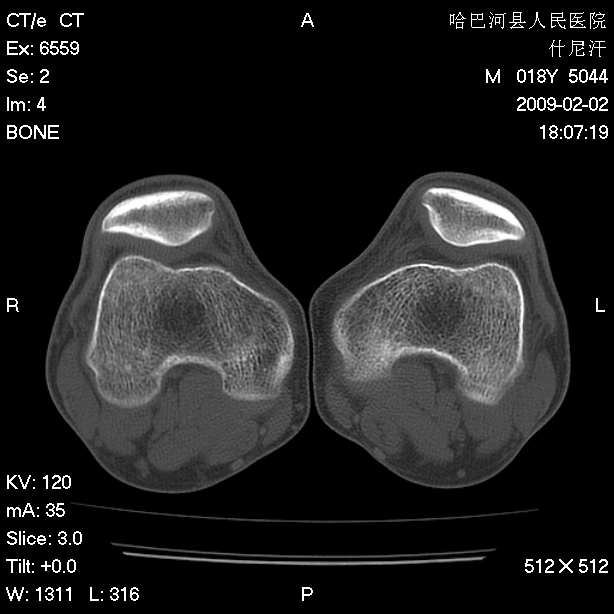

标题: CT17889:外伤后右膝关节反复疼痛3年余 [打印本页]

标题: CT17889:外伤后右膝关节反复疼痛3年余

ct未见明显异常。关节腔未见明显积液,半月板未见明显撕裂。但最好还是mri看看韧带及半月板情况。